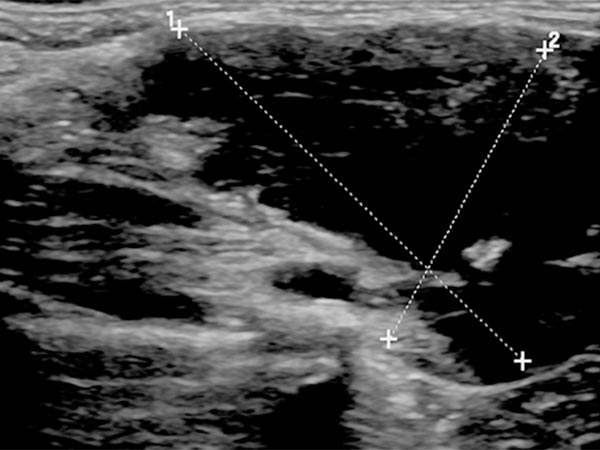

In der B-Bild-Sonographie (Längsschnitt) zeigt sich die venöse Malformation relativ homogen echoarm bis echofrei. Die venösen dysplastischen Gefäßkanäle sind mit dem Schallkopf kompressibel und enthalten flüssiges Blut.

In der B-Bild-Sonographie (Querschnitt) zeigt sich die venöse Malformation ebenfalls kombiniert echoarm bis echofrei. Die echoreicheren Anteile entsprechen Abschnitten der VM, in denen das enthaltene Blut bereits geronnen ist. In den echofreien Anteilen ist das enthaltene Blut noch flüssig. Zudem findet sich ein kleiner Phlebolith in der Läsion, dies ist praktisch pathognomonisch für eine venöse Malformation.